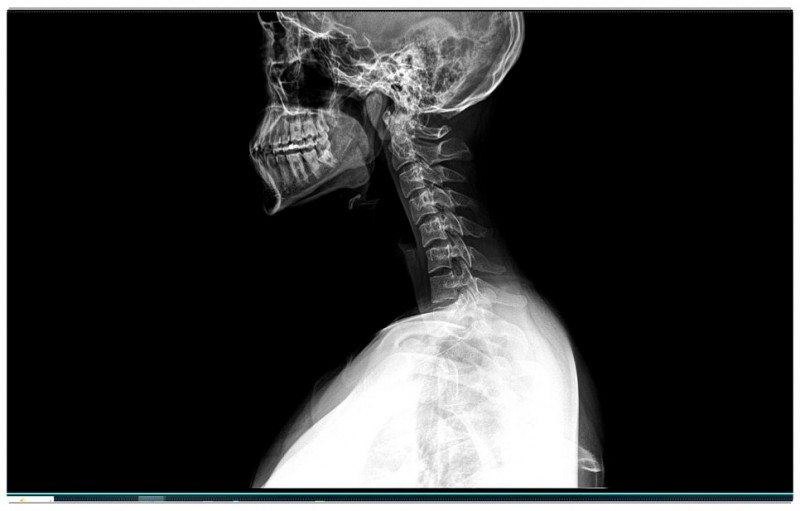

목과 어깨 통증, 구조적 원인부터 확인해야 합니다

하지만 실제로는 거북목과 굽은 등이 함께 진행되는 경우가 많습니다.

턱관절이 살짝 틀어지면 바로 아래 목뼈 1번, 2번이 영향을 받습니다.

이 부분에서 균형이 무너지면 목은 앞으로 빠지고,

굽은 등이 만들어지죠.

저는 거북목을 단순히 ‘목 하나의 문제’로 보지 않습니다.

턱관절 + 경추 + 척추 + 골반

이 네 가지를 하나의 구조로 함께 봅니다.